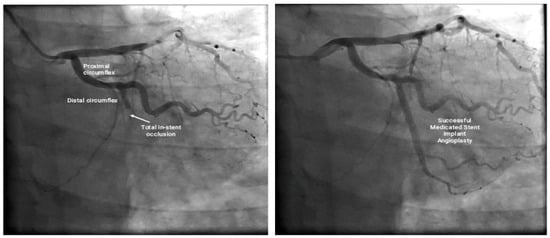

2. Case Presentation